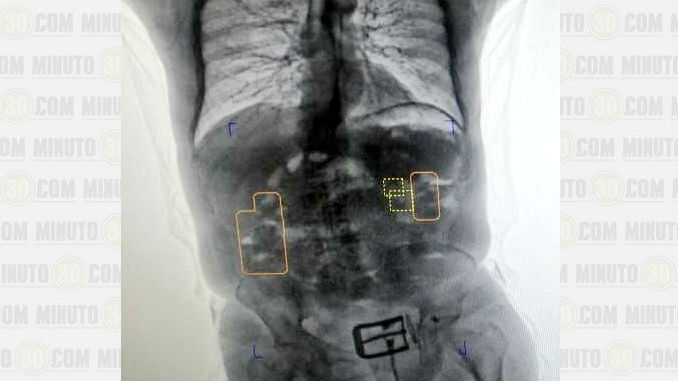

Minuto30.com- Un hombre de la tercera edad fue capturado en el Aeropuerto El Dorado de la ciudad de Bogotá cuando fue descubierto transportando consigo más de un kilo de clorhidrato de cocaína al interior de su cuerpo.

La droga fue descubierta en el abdomen y el hombre fue trasladado hacia un centro asistencial para efectuar la extracción de la misma.